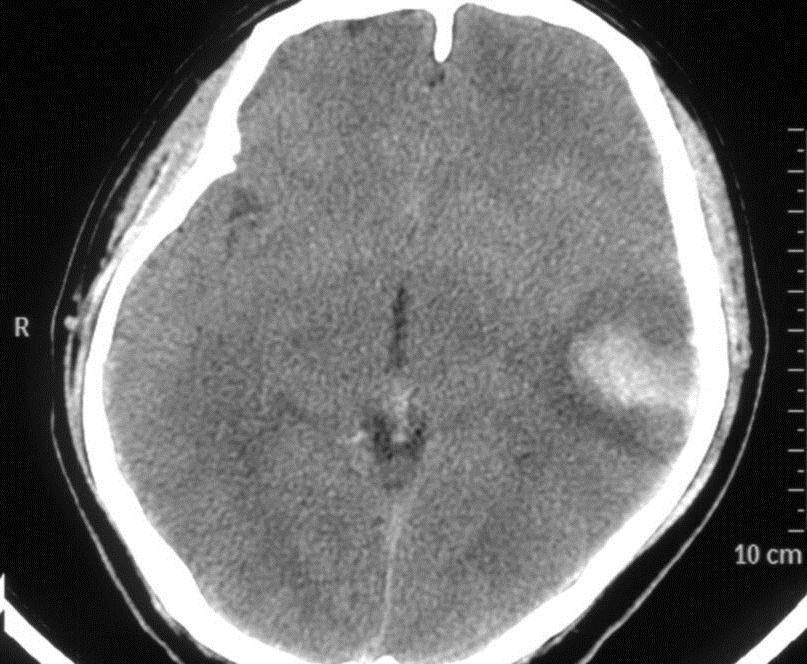

脑MRV:左侧横窦、直窦、窦汇显示不清,见图2

图2